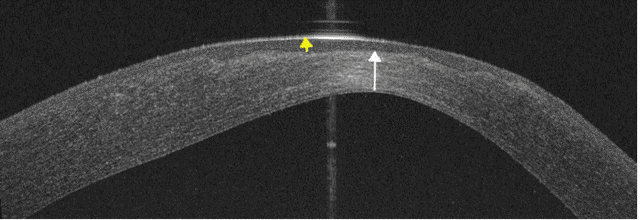

The unaided visual acuity in the affected eye improved to 0.66 LogMAR, further improving to 0.4 LogMAR with pinhole. The anterior segment optical coherence tomography (OCT) showed a significant posterior ectasia, paracentral stromal thinning (white arrow) (233 µm) with associated epithelial hypertrophy (yellow arrow) (92 µm) to mask the stromal thinning and irregularity (Figure 8 [Fig. 8]), and Pentacam revealed maximum keratometry of 57.3 D.

Figure 8: Anterior segment OCT of the left cornea 3 weeks post-operatively shows significant posterior elevation, apical stromal thinning (white arrow) (325 µm) and epithelial hypertrophy (yellow arrow) (92 µm) following surface healing.